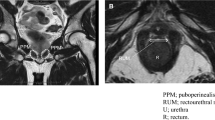

MRI was performed using the 1.5-T or 3.0-T MR system (Signa Premier or Signa HDx; GE Medical Systems, Waukesha, WI, USA or Ingenia, Philips Healthcare, Best, The Netherlands) with a multichannel anterior array coil combined with a multichannel posterior table coil. MRI was performed preoperatively and within 1 week of postoperative indwelling catheter removal. MRI was performed 30–60 min after urination. The estimated bladder capacity in each patient was 30–100 mL based on the MRI results. After multiplanar T2-weighted axial section imaging, an adequate sagittal section was created to capture the prostatic urethra. Sagittal dynamic MRI was performed at rest and during the abdominal pressure phase using a fast spin-echo sequence with the following parameters: repetition time/echo time, 1500–3716 ms/85–104 ms; flap angle, 90°; slice thickness, 6 mm; field of view, 300 mm; and imaging matrix, 224–352 × 156–224. Figure 1 illustrates the following measurements: distance from the distal end of the membranous urethra to the pelvic outlet (DMU-PO)11,12, distance from the bladder attachment to the pubic symphysis (BA-PS), the MUL, prostate length (PL), distance from the pubic symphysis to the prostate apex length (PAL)13, and the length from the bladder neck to the pubic symphysis (BN-PS)8. Figure 2 shows the dynamic mid-sagittal MRI after C-RARP and RS-RARP, performed preoperatively and postoperatively, at rest and with abdominal pressure. Figure 3 illustrates the measurement of the external urethral sphincter thickness, defined as the distance from the lowest point of the pubic bone to the anterior edge of the rectal wall, at rest and with abdominal pressure using MRI after C-RARP and RS-RARP. The compression distance was defined as the thickness of the external urethral sphincter at rest minus the thickness during abdominal pressure.

Parameters on mid-sagittal magnetic resonance imaging before (A, C) and 10 days after (B, D) robot-assisted radical prostatectomy. (A, B) The pelvic outlet (PO) (dashed red line) is defined as the line between the lowest end of the pubic bone and the tip of the coccyx. DMU-PO (red bidirectional arrowheads) is the distance from the distal end of the membranous urethra (DMU) to the midline of the PO. (C, D) Bladder attachment (BA) is defined as the upper edge of the attachment between the anterior bladder wall and abdominal wall. Pubic symphysis (PS) is defined as the upper edge of the PS. BA-PS (blue line) is the distance from the BA to the PS. Prostate length (PL) (yellow line). PS-to-prostate apex length (PAL) (orange bidirectional arrowheads) is defined as the distance between the extension lines of the suprapubic ridge line (dashed blue line) and the prostate apically. Membranous urethral length (MUL) (green line). Bladder neck to PS (BN-PS) (brown bidirectional arrowheads) is defined as the distance between the extension lines of the suprapubic ridge line and the lowest end of the bladder neck.